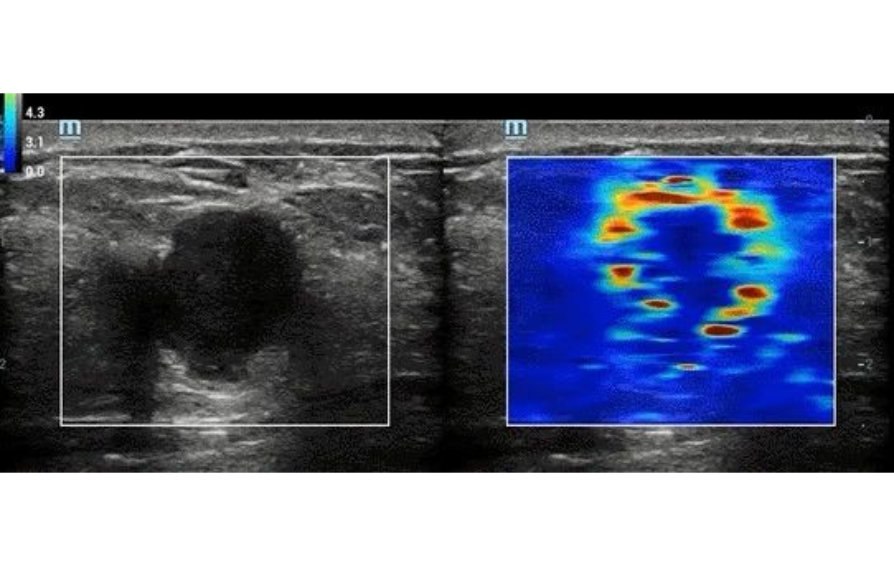

As the case implied, STE can significantly increase the odds of early detection by creating a safe ultrasonic shear wave to disturb soft tissue as it penetrates through the tissue. The ultrasound system can then analyze and evaluate tissue stiffness within a selected region in the scanning area.

After that, it will interpret and display real-time information in a color-coded image based on the softness and stiffness of the tissue which help to indicate what kind of anomaly is present.

For example, with STE, the possible presence of liver fibrosis can be detected for further follow-up or rule the possibility out by not seeing any stiff tissue.

ŌĆ£

ŌĆ£In ultrasonography today, we have to combine a perfect B-mode image, a perfect color Doppler image and a perfect STE image in order to have a global overview on whatŌĆÖs happening in the nodule and how suspect benign or malignant this nodule is.ŌĆØ said Pavlos Zoumpoulis, President and CEO of Diagnostic Echotomography SA, Greece